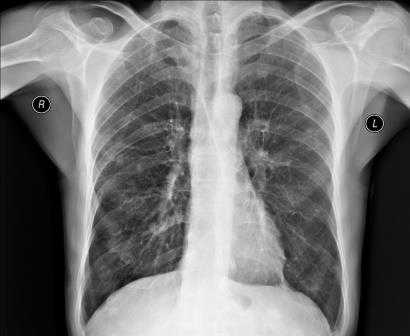

Рентген грудной клетки

Рентгеном грудной клетки называют проекционное рентгенографическое обследование. Его цель - оценка патологии органов, находящихся в этой полости, и близкорасположенных анатомических структур. Данная разновидность рентгена является, пожалуй, одним из самых распространенных рентгенографических исследований. Рассмотрим подробнее этот тип аппаратной диагностики.

Рентген грудной клетки: общая характеристика метода

Органы и ткани человека по-разному реагируют на ионизирующее излучение: чем выше их плотность, тем светлее на снимке объект. Выполнение рентгенографии грудной клетки позволяет изучить мягкие ткани, кости этой части тела и анатомические структуры, находящиеся в исследуемой полости (легкие, плевру, средостение).

В зависимости от показаний пациенту может быть назначен обзорный или прицельный рентген грудного отдела. В первом случае получают изображения всех органов грудной клетки. На снимке обзорной рентгенографии хорошо видны дыхательные пути, лимфоузлы, сосуды, бронхи, трахея, легкие и сердце. Прицельная рентгенография направлена на исследование конкретного органа или его части и обеспечивает оптимальное изображение патологического очага для диагностики.

Во время расшифровки полученного рентгеновского снимка, прежде всего, оценивается качество изображения, а значит, и насколько правильно осуществлена процедура. Если рентгенография была сделана в неверной проекции и снимок имеет неточности, то заключение на его основании сделать достаточно сложно. При рентгене легких, например, оценивается размер легких, их форма, структура тканей и легочных полей, состояние воздушности и расположение внутренних органов.

Если у пациента пневмония, на снимке будут видны ярко выраженные отклонения от нормы - интенсивные дополнительные ткани как на прямой, так и на боковой рентгенограмме. Присутствие на снимке особой прикорневой формы, напоминающей по виду крылья бабочки, говорит о венозном застое в области малого круга. На отечность легочной ткани будут указывать неравномерные хлопьевидные затемнения на изображении.